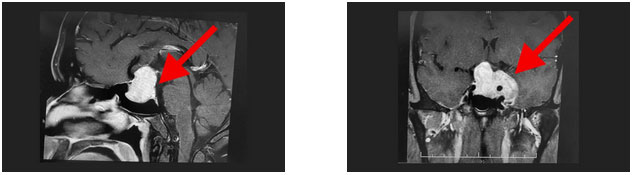

鞍區(qū)MRI平掃+增強(qiáng)顯示:蝶鞍擴(kuò)大,鞍底骨質(zhì)下陷,鞍內(nèi)垂體上緣隆起,鞍隔處見“腰癥”;增強(qiáng)掃描,病變早期和延遲期持續(xù)強(qiáng)化,最大層面約4.5*3.7*3cm;鞍上視交叉受壓上抬,左側(cè)海綿竇及左側(cè)頸內(nèi)動脈受包繞。檢查催乳素超3000μIU/mL,遠(yuǎn)超正常值。

神經(jīng)外科6B病區(qū)潘仁龍主任、李士其教授、吳治群博士會診后考慮為侵襲性泌乳素型垂體巨大腺瘤,正是垂體瘤導(dǎo)致小劉性功能下降,并且腫瘤已經(jīng)壓迫視神經(jīng)導(dǎo)致視力下降,手術(shù)指征明確。

▲ 影像顯示垂體占位,侵及左側(cè)海綿竇